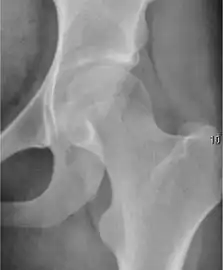

Projectional radiography ("X-ray") is the first imaging technique of choice in hip pain, not only in older people with suspected osteoarthritis but also in young people without any such suspicion. In this case plain radiography allows categorization as normal hip or dysplastic hip, or with impingement signs, pincer, cam, or a combination of both.[1]

X-Ray

Projectional radiography ("X-ray") is currently useful not only in older people in whom osteoarthritis of the hip is suspected but also in younger people without osteoarthritis, who are being evaluated for femoroacetabular impingement (FAI) or hip dysplasia.[1]

Plain radiography allows us to categorize the hip as normal or dysplastic or with impingement signs (pincer, cam, or a combination of both). Besides these, pathologic processes like osteoarthritis, inflammatory diseases, infection, or tumors can also be identified (Figure 1).[1]